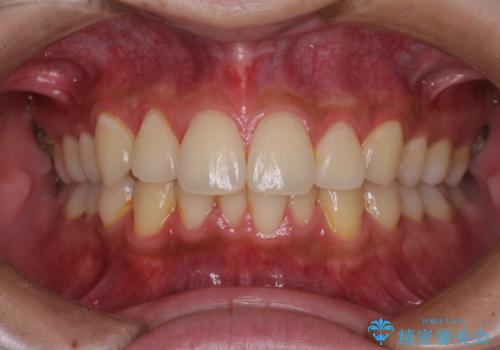

矯正治療の後戻りをインビザライン・ライトで解消

- 矯正治療の後戻りを気にして来院された患者様です。

後戻りは軽微であったので、インビザライン・ライトにより矯正治療を行うこととしました。